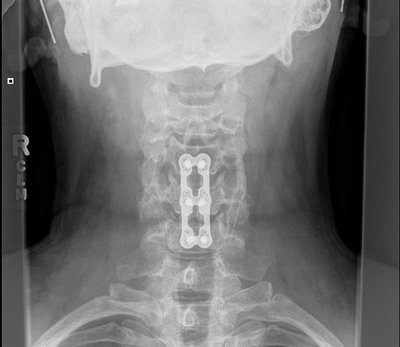

Saw my surgeon today with fresh X-rays. (below)

He likes how it is looking, wants to see me again in three months, at which time we'll discuss my return to flying. Thus grounded for the summer, I'll have to miss Hyner this weekend and July 4th.

My fusing plugs and titanium shield.

Front View

Wow, Cragin, those are some impressive x-rays. Hope you can make it out to Hyner for Labor Day.